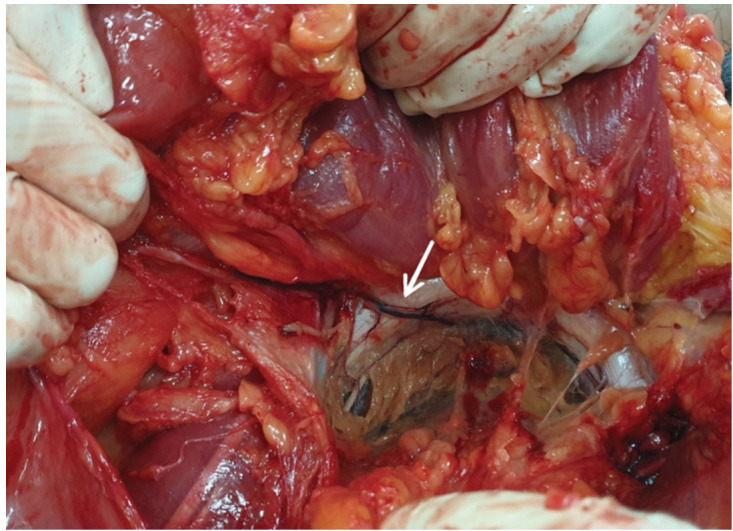

Introduction: Corona Mortis (CMOR) is a term used to describe an anatomical vascular variant of retropubic anastomosis located posterior to superior pubic ramus. We aim to provide sufficient data on the incidence, morphology and mean location of 'crown of death' in Asian population. Other objectives include to assess the relationship between CMOR incidence with gender, race and age.

Materials and methods: This is a cross-sectional cadaveric study involving 164 randomly selected fresh multiracial Asian hemipelves (82 cadavers). Hemipelves were dissected to expose and evaluate the vascular elements posterior to superior pubic rami. Data were analysed using Chi-Square, t-test and with the help of IBM SPSS Statistics v26 software.

Results: CMOR was found in 117 hemipelves (71.3%). No new morphological subtype was found. The mean distance of CMOR to symphysis pubis was 54.72mm (SD 9.35). Based on the results, it is evident that precaution needed to be taken at least within 55mm from symphysis pubis during any surgical intervention. The lack of statistically significant correlation between CMOR occurrence and gender, race and age suggest that the incidence of CMOR could be sporadic in manner.

Conclusion: We conclude that CMOR is not just aberrant vessel as the incidence is high and this finding is comparable to other studies. The mean location of CMOR obtained in this study will guide surgeons from various disciplines in Asia to manage traumatic vascular injury and to perform a safe surgical procedure involving the pelvis area.